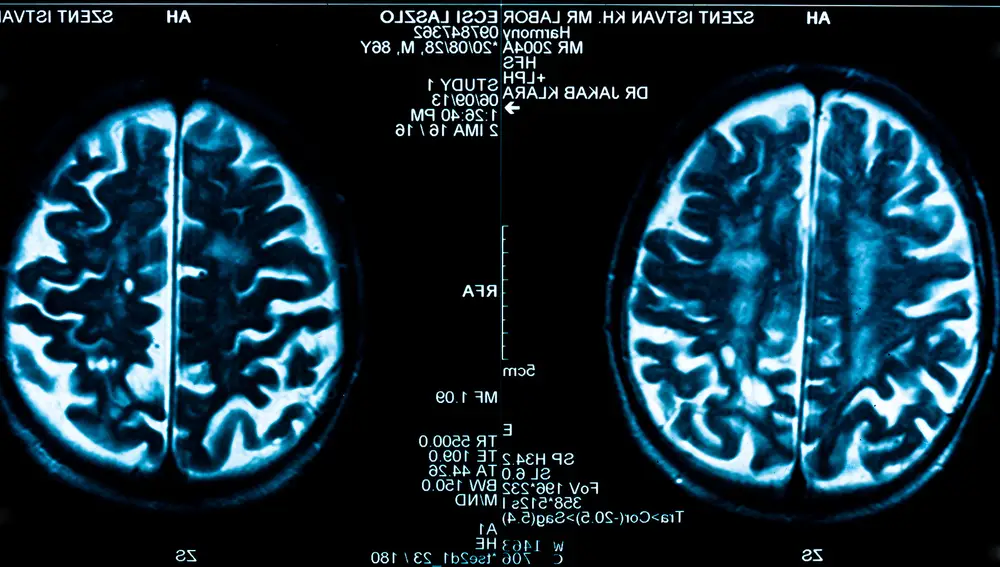

Un estudio reciente ha descubierto que el proceso de crear recuerdos puede causar daño cerebral temporal, pero esto se traduce en una mayor resistencia neuronal.

Cuando aprendemos algo nuevo, nuestro cerebro experimenta un proceso complejo que puede ejercer presión sobre su funcionamiento normal. Este proceso implica la formación de nuevas conexiones neuronales y la reorganización de las existentes, lo que puede generar estrés y desafíos para el cerebro. Pero un nuevo estudio da más luz sobre este asunto.

Un reciente estudio internacional, que se ha llevado a cabo en ratones y ha sido publicado en la revista científica Nature, ha revelado que la formación de nuevos recuerdos podría causar daños temporales en el cerebro, pero con un propósito protector a largo plazo. La investigación mostró que al crear nuevos recuerdos, se activan genes relacionados con la inflamación. Estos marcadores inflamatorios permanecían activos durante una semana, después de la cual las neuronas afectadas se volvían más resistentes a daños futuros.